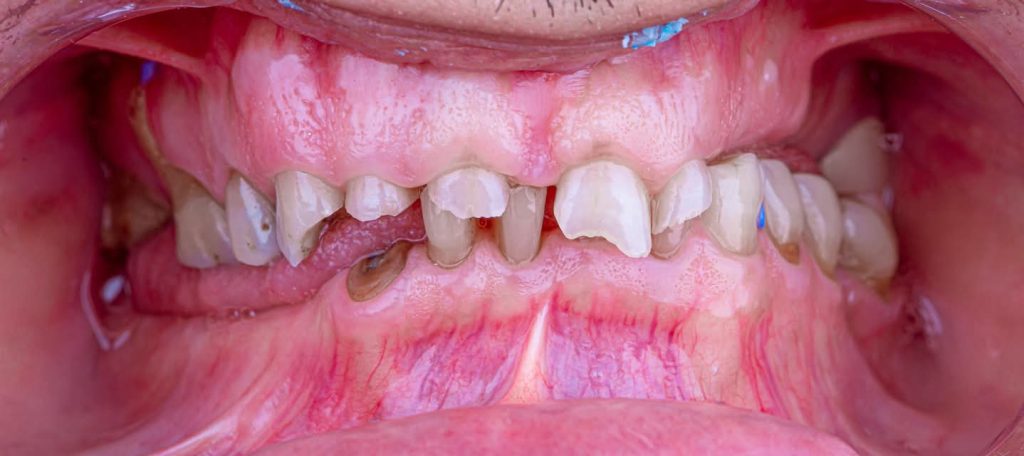

1. Diagnostic Phase:

This phase began with:

Extraoral examination: Included palpation of the masticatory muscles. The patient showed no signs of Temporomandibular Disorders (TMD).

Intraoral examination and determination of the vertical dimension at occlusion and rest using the phonetics method. This involved the physiologic rest position and interocclusal distance protocol, where the patient was instructed to say the labial “M” sound (e.g., in EMMA) without tensing the lips, allowing the mandible to settle in the rest position.

Fortunately, the patient was classified as Category I according to Turner and Missirlian’s (1984) classification, with an interocclusal space exceeding 5 mm.